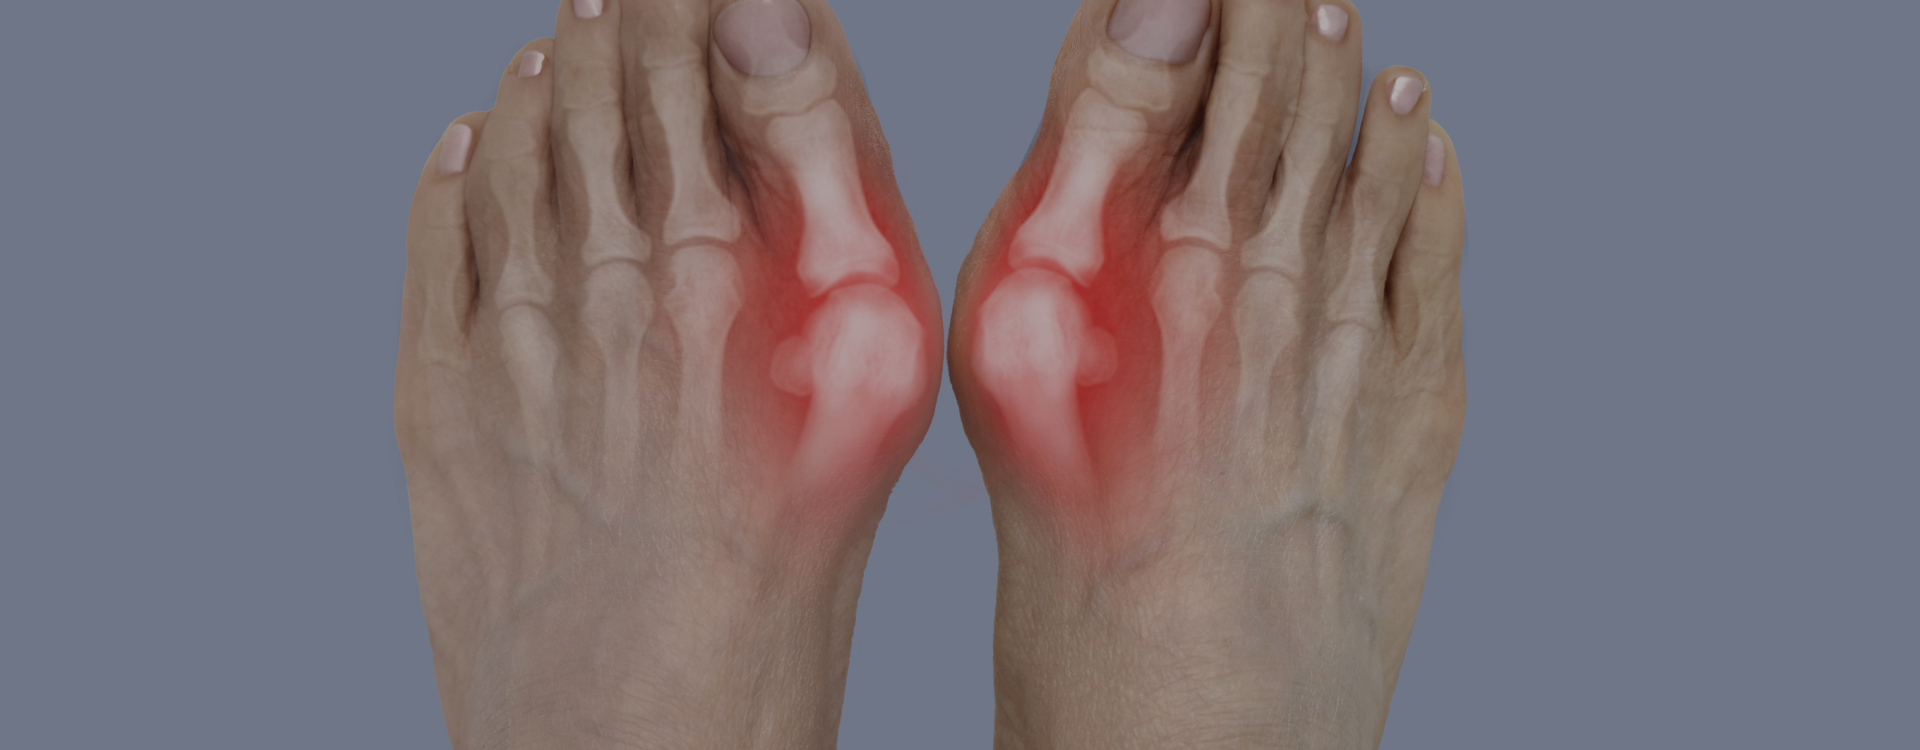

기능 문제뿐 이니라 미용적 스트레스까지

유발하던 무지 외반증.

• 01.통증/염증으로 보행이 불편한 경우

• 02.변형 각도 20도 이상 (3~4단계)

• 03.깔창·신발로 호전되지 않는 진행성 무지외반증

• 04.미용적으로 개선을 원하는 경우